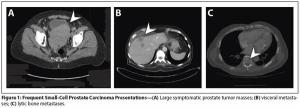

Aggressive variants of prostate cancer often take the form of neuroendocrine or small-cell carcinomas, which frequently lack androgen receptor expression and respond poorly to hormonal therapies.